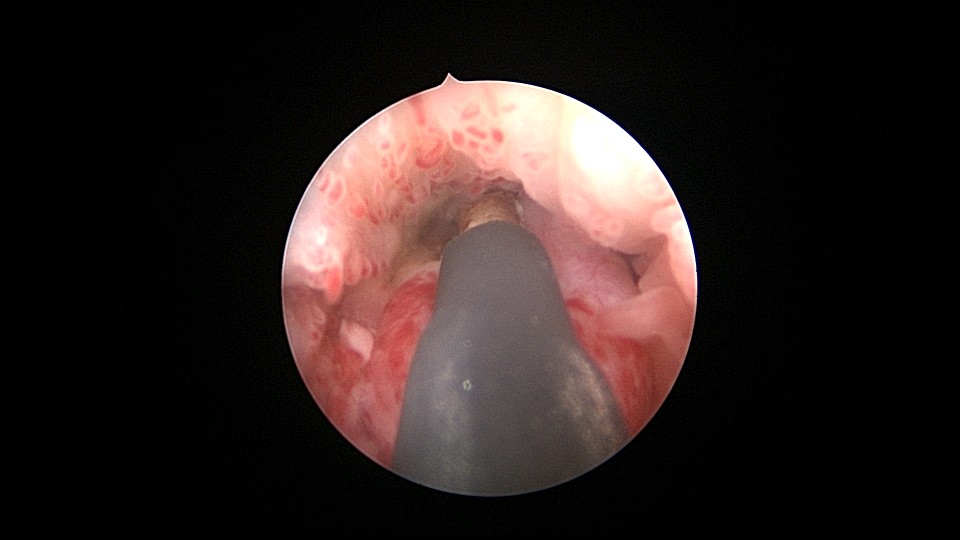

患者55岁,G1P1,顺产1次。安环31年,绝经3年,妇科检查发现宫颈外口息肉,B超宫腔未见分离暗区。子宫前位,宫腔镜见宫颈管下段多发息肉,宫颈内口粘连,宫腔少许淡黄色脓液流出,宫型环位置正常,被镜鞘推挤变形。助手单极电针切除宫颈管息肉时进针过深,引起较多出血,视野不清楚,接手手术,先止血、切除息肉,然后异物钳取出节育环,宫腔无其他异常。病检为宫颈管息肉。